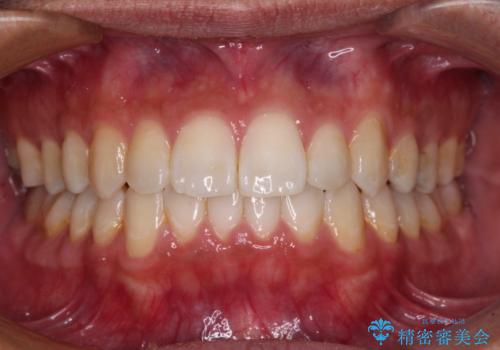

![[ インビザライン矯正 ] マウスピース矯正で治す、前歯のガタつきの症例 治療前](https://seimitsushinbi.jp/wp/wp-content/uploads/2022/02/324533f54aaa29eca08b0a9fdd3af7e2-500x350.jpg?v=1644473292)

![[ インビザライン矯正 ] マウスピース矯正で治す、前歯のガタつきの症例 治療後](https://seimitsushinbi.jp/wp/wp-content/uploads/2022/02/IMG_1698-500x350.jpg?v=1644473356)